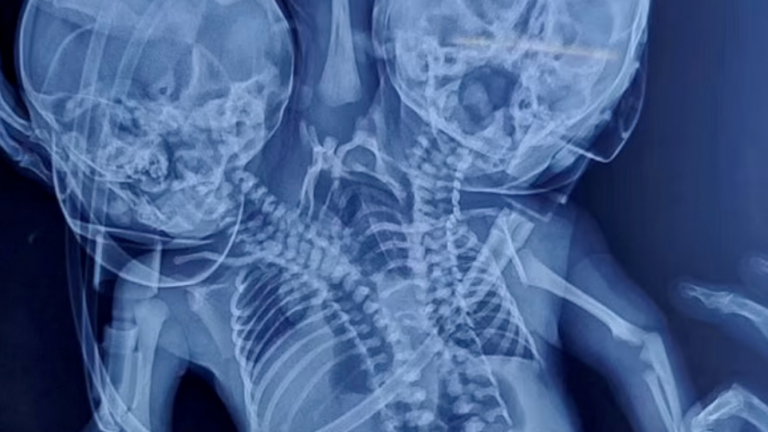

¡Caso insólito! Mujer esperaba dar a luz mellizos pero nació un bebé con dos cabezas